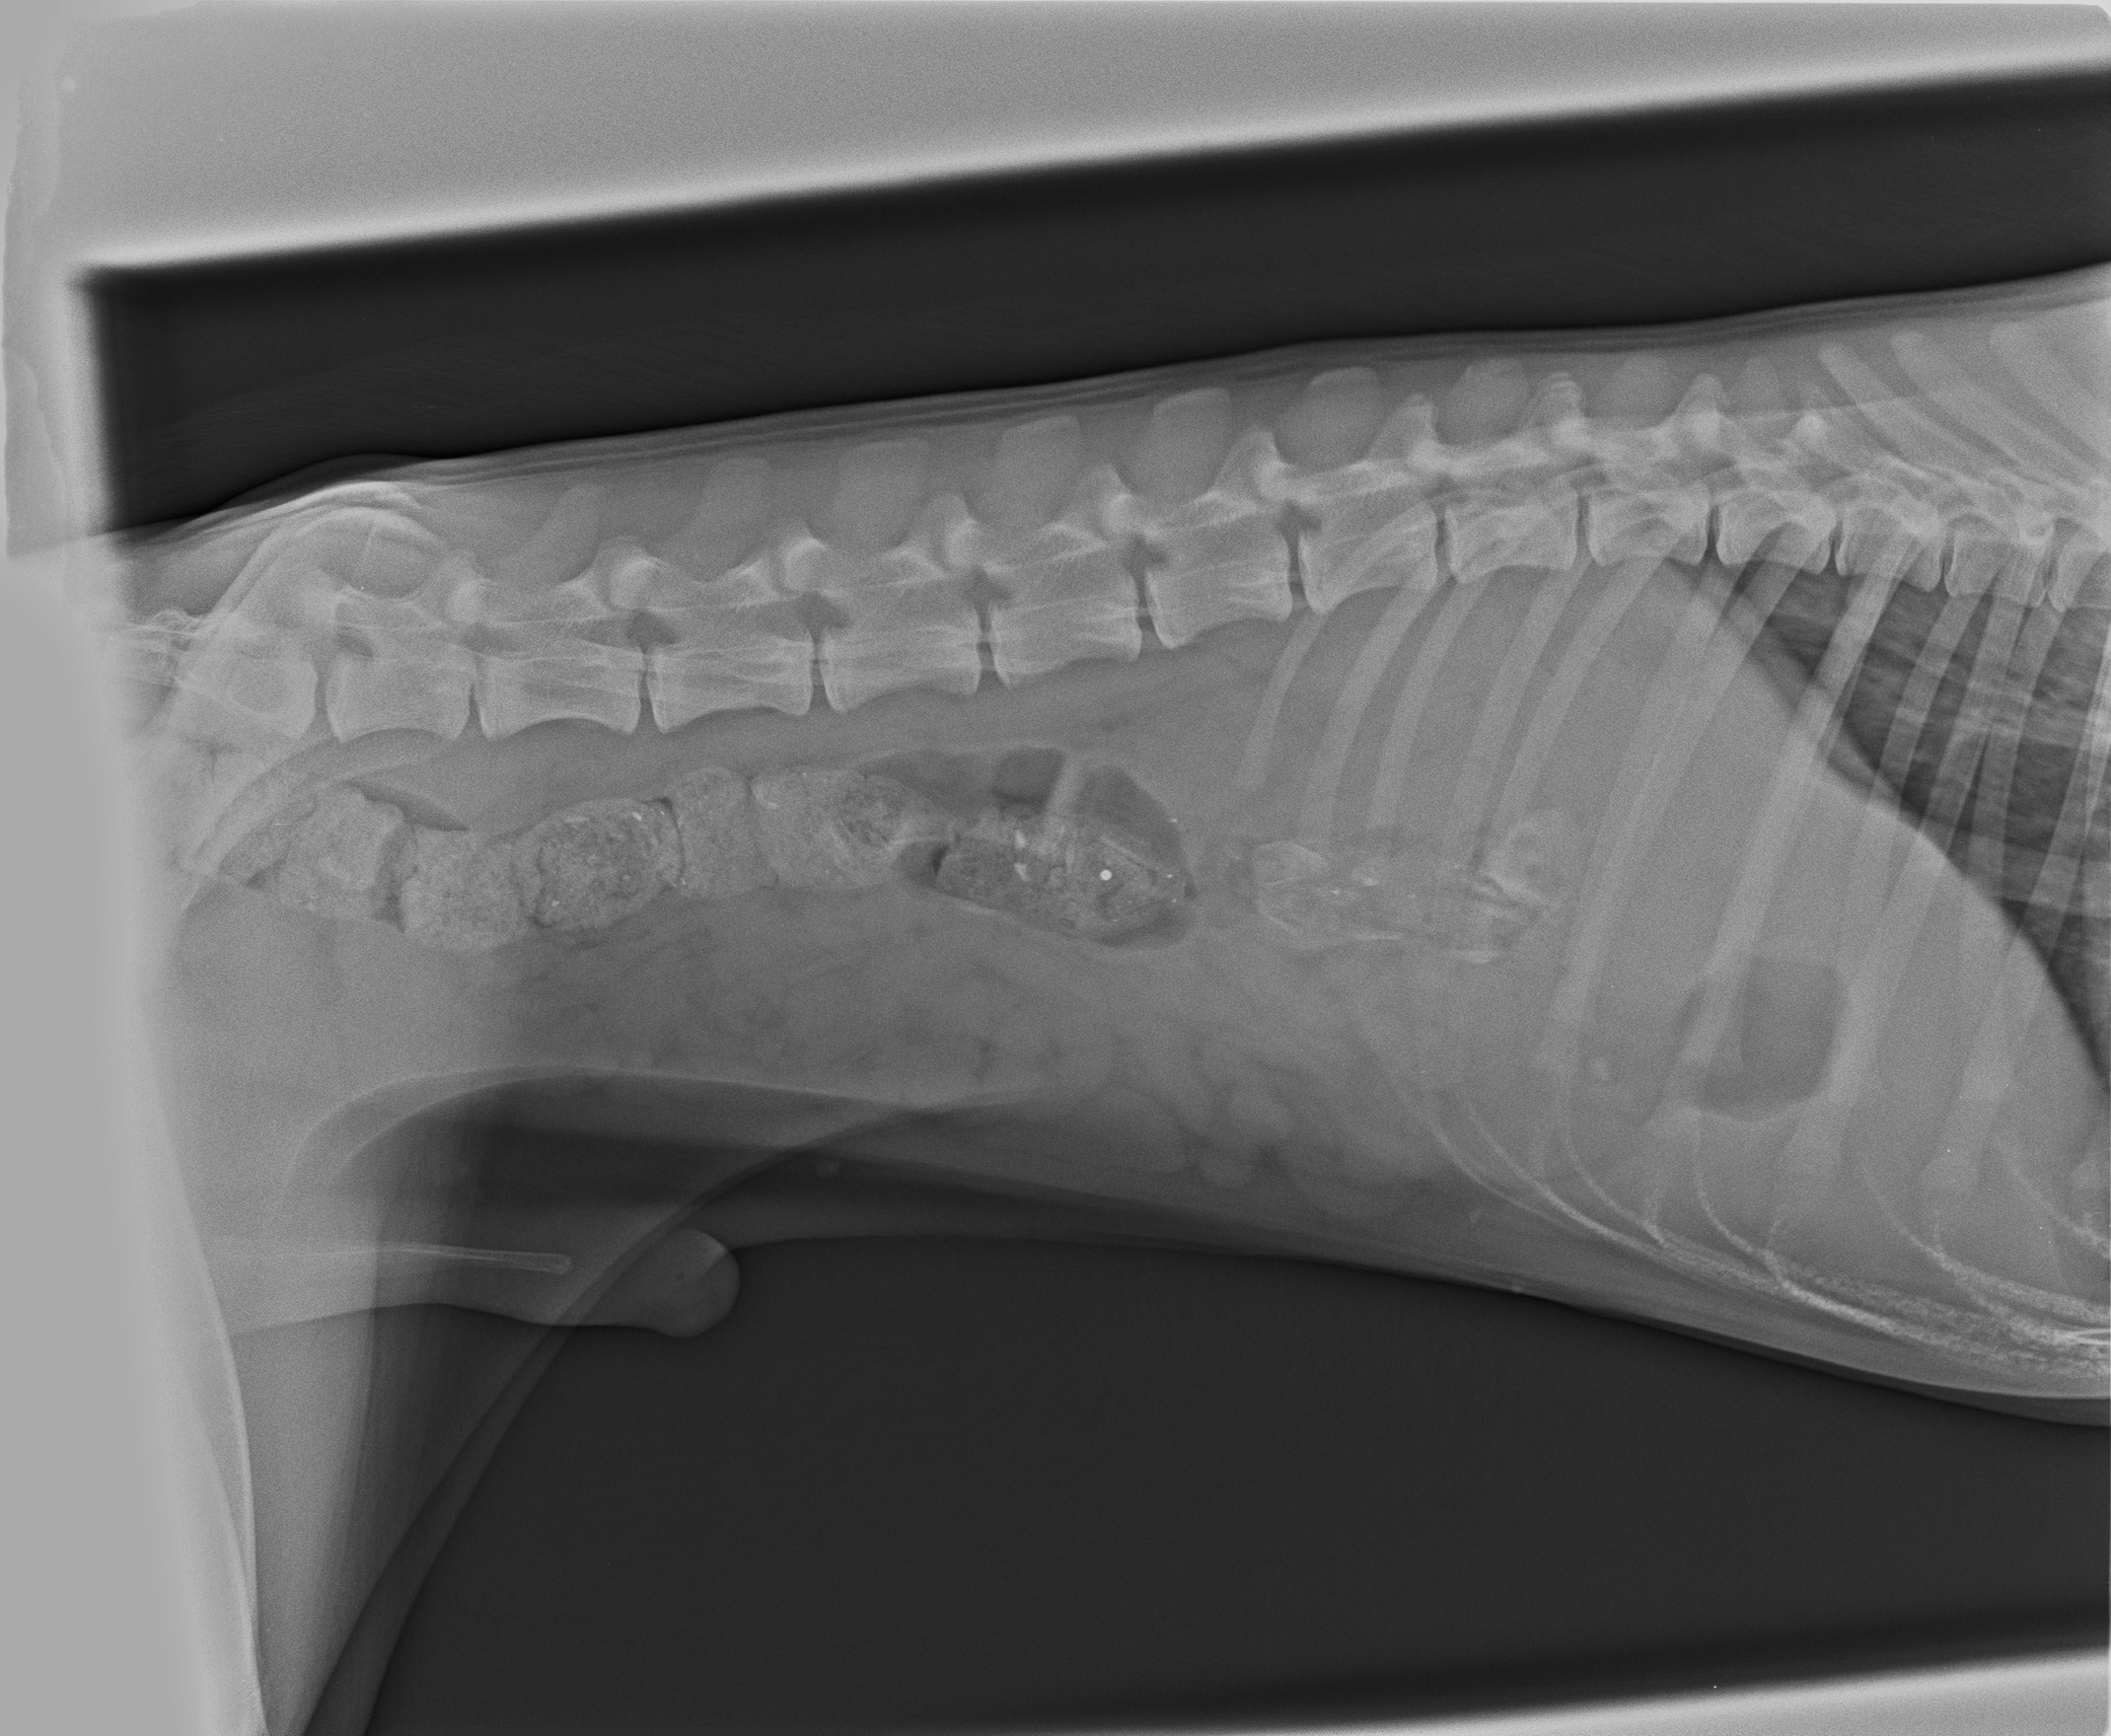

ד"ר שרית החליטה לבצע צילום רנטגן במנח לטרלי של חלל הבטן,שחשף מוקדים רדיואופקיים, אשר היו פזורים לאורך לולאות המעי.

ממצאים אלה העידו על הימצאות שאריות עצם במערכת העיכול, בשלבי מעבר שונים.